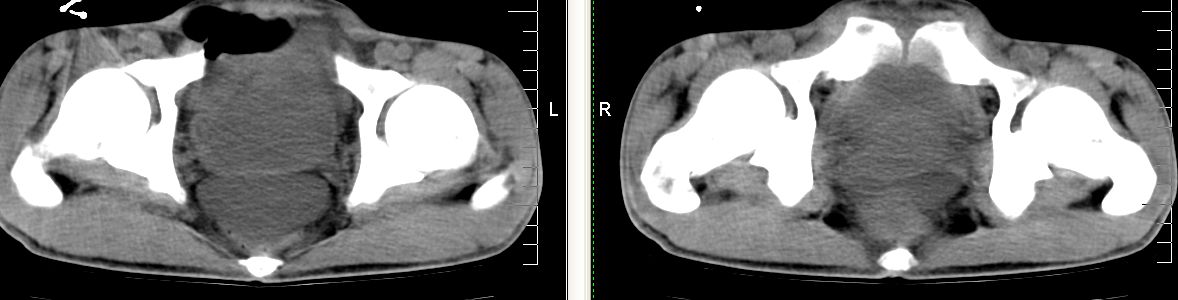

m 29 肺tb患者,目前诉下腹疼痛 t39度 腹韧,有压痛,可触及3x4cm包块

脾脏多发低密度灶,肠系膜及腹膜后见多发大小不等结节状影,右结肠旁沟见低密度影,结合病史考虑:脾结核,肠系膜及腹膜后淋巴结结核,少量腹水。

脾脏多发低密度灶,左侧肾上腺见块状病灶,密度不均,盲肠升结肠肠壁明显增厚,左下腹似可见肠壁增厚,肠系膜及腹膜后见多发大小不等结节状影,右结肠旁沟见低密度影,1淋巴瘤可能大,2结合病史考虑:脾结核,左侧肾上腺结核,肠系膜及腹膜后淋巴结结核,少量腹水待除外,

左肾上腺肿大及脾脏多发低密度灶腹膜后见多发淋巴结舯大

考虑为肾上腺及脾腹膜后多发转移灶